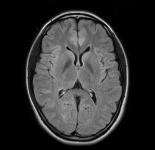

頭部MR検査

画像コントラストが優れており、脳の詳細な構造を描出することが可能です。